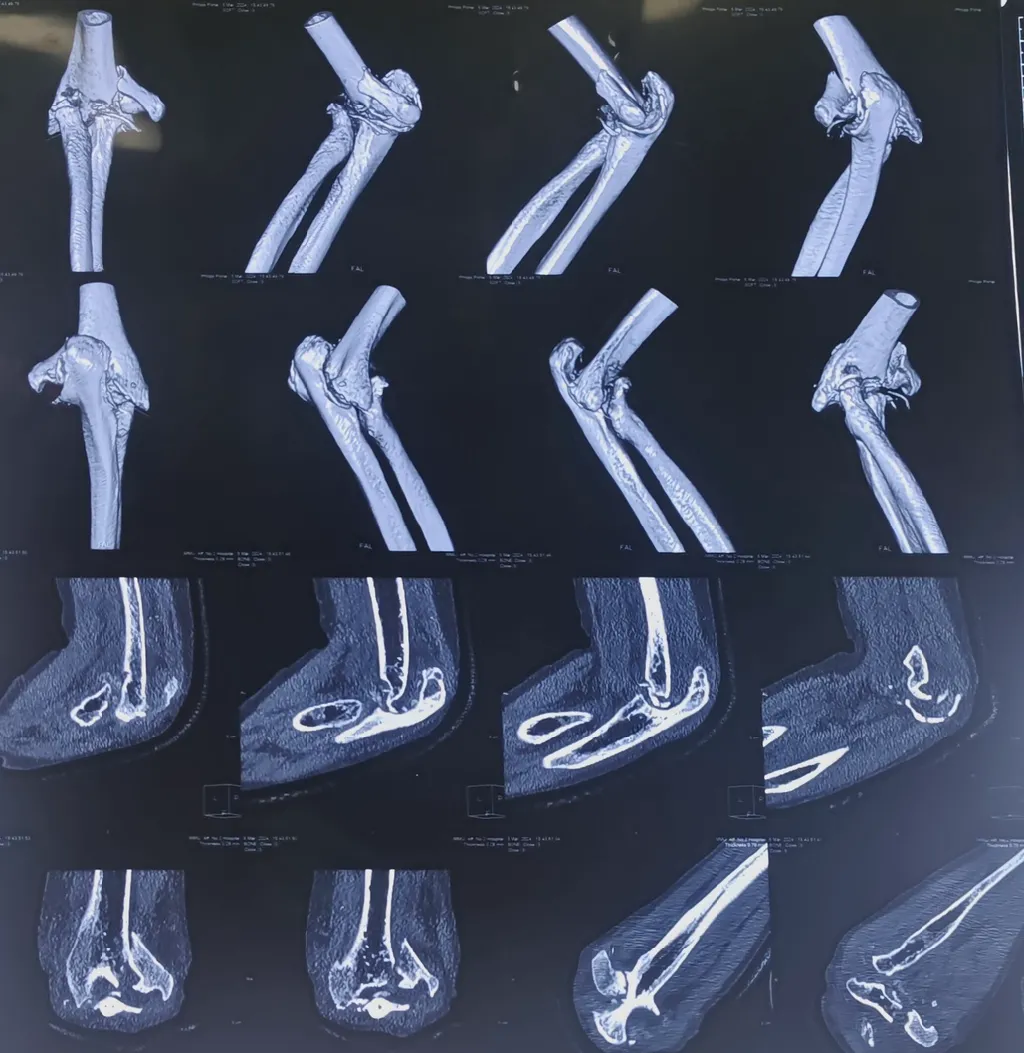

为深入推动医院高质量发展及京蒙协作临床重点专科建设项目落地见效,进一步推动创伤外科学科建设持续发展,近日,91直播 客座教授、北京积水潭医院李庭教授受邀来91直播 会诊并指导手术。李庭教授高度重视91直播 创伤急救外科学科建设工作,为91直播 创伤外科中心A区一位右肱骨髁间骨折、右上尺桡关节脱位、右肘关节粉碎性骨折并患有严重基础病的患者进行会诊并指导手术。

患者孙某,65岁,患者于家中不慎摔伤右上臂,患者为求进一步诊治来91直播 就诊,被诊断为:右肱骨髁间骨折、右上尺桡关节脱位、肝血管瘤、单纯性肾囊肿。另外,患者有类风湿病史38年。手术治疗的目的是尽最大限度恢复肘关节的功能。